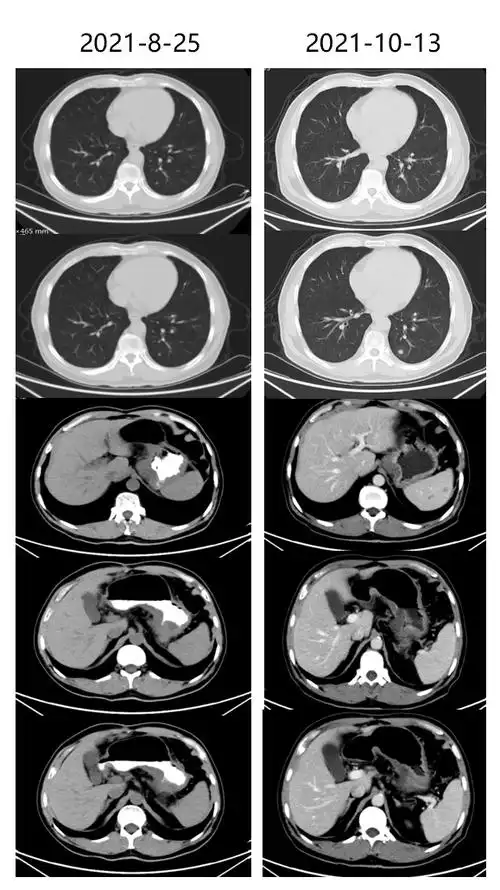

百启新生未来可期逆转化疗耐药替雷利珠单抗治疗晚期胃癌病理完全缓解